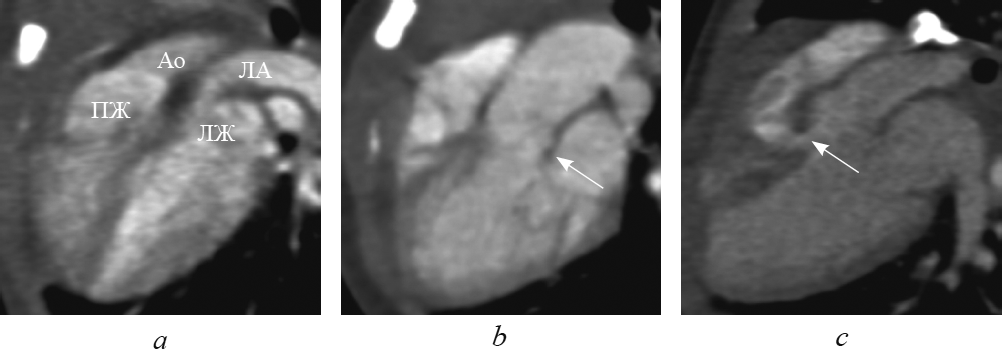

Рис. 7. В реформации по длинной оси левого желудочка при транспозиции магистральных сосудов: выходные тракты и магистральные артерии расположены параллельно (а); определяются митральное полулунное фиброзное продолжение (b, стрелка) и дефект межжелудочковой перегородки (c, стрелка). Ао — аорта; ЛА — легочная артерия; ЛЖ — левый желудочек; ПЖ — правый желудочек

Fig. 7. Long-axis of left ventricle reformation in great arteries transposition: outflow tracts and great arteries are parallel (а); semi-lunar fibrous prolongation (b, arrow) and interventricular sept defect (c, arrow) are determined. Ао – aorta; ЛА – pulmonary artery; ЛЖ – left ventricle; ПЖ – right ventricle

Достоверно визуализировать митрально-полулунное фиброзное продолжение, представляющее собой фиброзный контакт легочного клапана с митральным клапаном, при транспозиции удалось в 10 случаях (рис. 7, b). Дефект межжелудочковой перегородки визуализировался во всех случаях (рис. 7, c). В реформации по длинной оси левого желудочка удалось определить стеноз выходного тракта левого желудочка (рис. 8).

Рис. 8. В реформации по длинной оси левого желудочка при транспозиции магистральных сосудов определяется сужение выходного отдела левого желудочка. Ао — аорта; ЛА — легочная артерия; ВО — выходной отдел; ДМЖП — дефект межжелудочковой перегородки; ЛЖ — левый желудочек; ЛП — левое предсердие; ПЖ — правый желудочек

Fig. 8. Long-axis of left ventricle reformation in great arteries transposition: narrowing of the output portion of the left ventricle is determined. Ао – aorta; ЛА – pulmonary artery; ВО – the output portion; ЛЖ – left ventricle; ЛП – left atrium; ПЖ – right ventricle